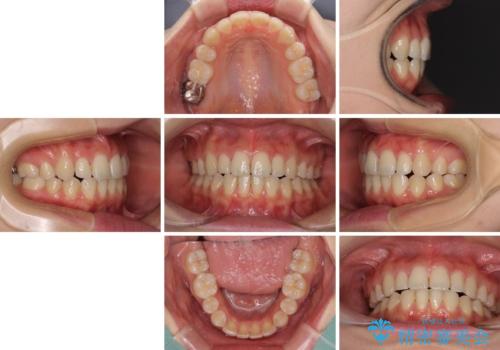

前歯2本が欠損 抜歯矯正でデコボコを治す

- 前歯のデコボコを気にして来院された患者様です。

本人は気づいていませんでしたが、下顎前歯が2本欠損しており、上下の歯列がアンバランスとなりデコボコになっていました。

上下のバランスを取るため、上顎左右第一小臼歯2本を抜歯し、ワイヤー矯正を行うこととしました。

抜歯矯正を行ったことで、デコボコが改善されただけでなく、口元も下がったことで口が閉じやすくなりました。